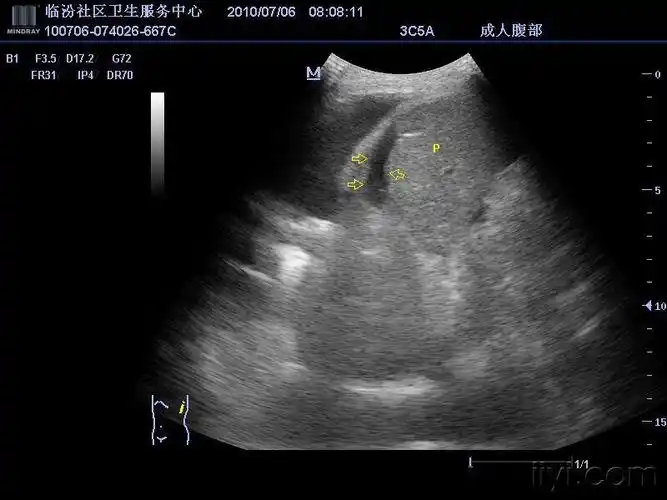

脾破裂——zengerya - 超声医学讨论版 - 爱爱医医学论坛

【答案解析】_脾破裂声像图特征:①脾包膜,边缘不规则,连续中断②脾周